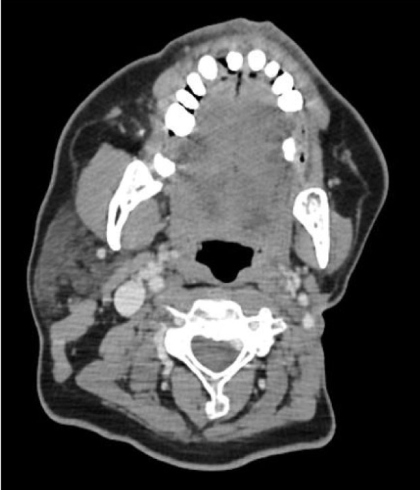

2001年,刚参加工作没多久的M先生发现自己的左侧脸颊和耳朵附近出现了一个肿块,去医院检查后发现竟然是一种罕见但发展迅速的恶性肿瘤--腮腺癌(涎腺癌中发生率最高的一种恶性肿瘤)。

去医院进行详细的检查后证实,腮腺癌局部复发,更糟的是出现了颈淋巴结转移,医生说已经没有手术机会了。M先生接受了化疗来控制这种发展迅速的恶性肿瘤,不幸的是,治疗无效,M先生的复发的肿瘤明显增多并且还出现了肺部的转移。

2019年初,M先生开始服用恩曲替尼。在治疗前,他左侧腮腺的肿瘤已经有橘子那么大(7公分),并且肿瘤已经破溃,需要始终缠着纱布。在恩曲替尼治疗2个月后,病灶以肉眼可见的速度显著缩小。更让大家惊喜的是,在治疗后6个月的复查结果显示,M先生腮腺的病灶已经完全消失了,同时,肺部的转移灶也全部消失,评效达到完全缓解(CR)!